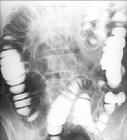

氣鋇雙重造影示回盲部1、X線檢查:腹部平片,可見擴張的腸管(梗阻病變近端腸管)。小腸造影:顯示鋇劑從吻合口逆行進入曠置的腸管,並且有一部分通過狹窄部位逆行進入曠置的近端腸管,然後再由順蠕動將鋇劑推入吻合口遠端,或逆蠕動到吻合部位;